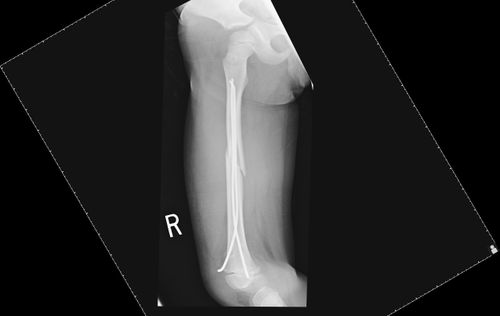

He was treated by flexible retrograde intramedullary rods with closed insertion under image guidance with good pos-top results.

His rods will be removed at three months and he is expected to make a full recovery.